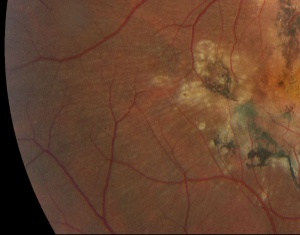

The disease is typically characterized by early-onset drusenoid deposits presenting at the posterior pole, peripapillary area, center of the macula, and along vascular arcades. The deposits are characteristically described as multiple "radially elongated" or "honeycomb pattern" small drusen in early stages, but can become indistinguishable from deposits in advanced AMD in later stages as they become larger and more confluent. Involvement nasal to optic disc is a typical feature. Pigmentary changes often occur as the disease progresses . CNVM can form, with subsequent scarring, and in advanced stages geographic atrophy can occur in the areas of confluent drusen. Early stages may have bilateral symmetric basal laminar drusen.

Spectral domain optical coherence tomography (SD-OCT) imaging can reveal focal dome-shaped, saw-tooth, or diffuse hyperreflective deposits with elevation between the RPE and Bruch's membrane, usually becoming more confluent over time[11]. Early in disease, the outer retina (photoreceptors) may remain intact, but later stages can show variable or diffuse ellipsoid zone loss, as well as outer and inner segment disruption. OCT can also reveal hypo-reflective fluid from a corresponding neovascular membrane. Diffuse retinal atrophy can be seen in later stages, however outer retinal changes are not often seen outside of areas with sub-RPE changes[12].

Fundus autofluorescence (FAF) can reveal hypo or hyper-autofluorescence of drusen, with one study showing larger drusen were more typically hyper-autofluorescent [11]. This increased autofluorescence associated with drusen in DHRD (and in other genetic drusen forming maculopathies) seems to be in contrast to typical drusen of AMD, where there is generally little correspondence between distribution of drusen and FAF[11][13]. Central areas may be hypo-autofluorescent due to central geographic atrophy and loss or dysfunction of RPE.

Fluoroscein angiography (FA) can reveal presence of CNVM with leakage, and large drusen are typically hyper-fluorescent in late stages[11]. Variable hypo or hyperfluorescence can be seen in areas of pigmentary changes, atrophy, and scarring. Indocyanine green angiography (ICG) can also be used to differentiate between two types of drusen. This imaging modality has shown different patterns of staining between large central drusen and small radial drusen. Large central drusen initially present as hypofluorescent, and then become hyperfluorescent spots surrounded by halos of hypofluorescence in the late phases. Small radial drusen on the other hand, present with hyperfluorescence in early phases and decreased fluorescence in late phases. [14]